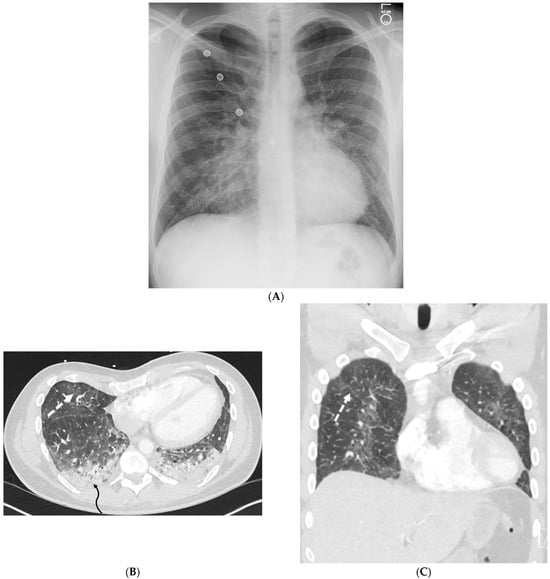

5.2. Kaposi’s Sarcoma